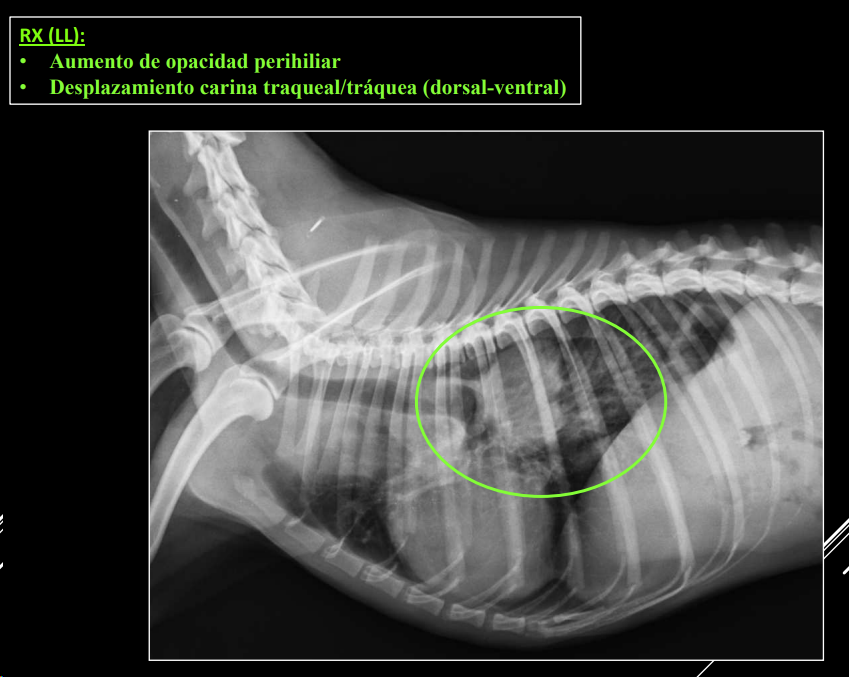

Hiliares/Perihiliares: alteraciones esofágicas, tumor base cardiaca, linfoadenopatía traqueobronquial, masa tiroidea ectópica.

-

Masa de opacidad tejido blando que desplaza la traquea y la bifurcación bronquial.

Puede ser por los nodulos parabronquiales, esofagico o por masa en el pulmón